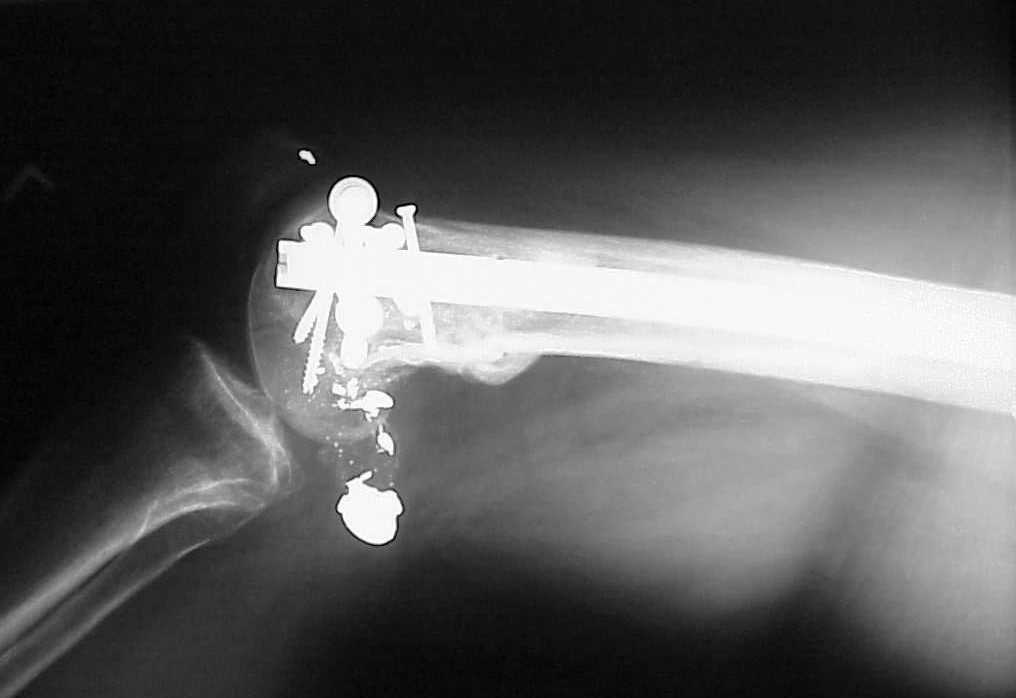

See attached case that was done several years ago before LISS. He had comminuted trochlea and anterior blocking screws were used to prevent anterior IMN cut-out.

Да, примерно так и сделали. Надо было, пожалуй, кончик гвоздя еще спилить, чтобы отверстие было еще дистальнее. Англоязычные коллеги еще

советовали винты в передне-заднем направлении вводить, но что-то не увидел, где там подходящее место.

Since it was done closed the shaft will heal or at worst need an exchange IMN.

Nice job.

Мы пошли на операцию с планом попытаться сделать закрытый интрамедулярный, а не получится - сделать аппаратом. Посчитали, что получилось, хотя на еженедельной конференции ожидаются некоторые проблемы с объяснениями ;-)

Насчет стабильности для ранней нагрузки, конечно, сомнительно, но при таком повреждении ранняя нагрузка противопоказана в любом случае. Для ранних движений Должно хватить. Снимки в следующем сообщении.